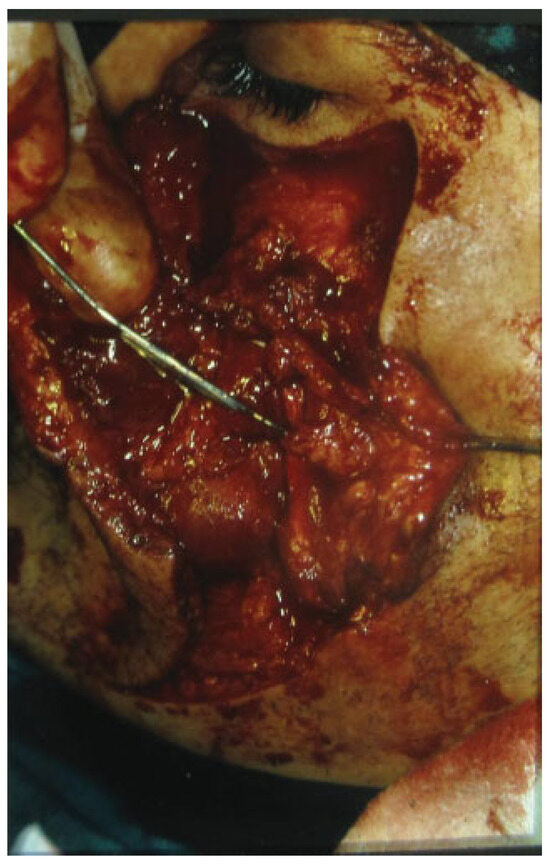

Figure 4. The proximal stump of the left transected parotid duct is identified with a lacrimal probe.